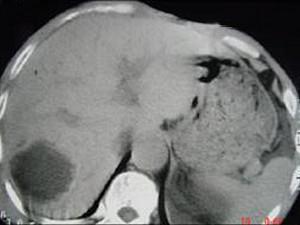

问题 女,62岁,右上腹隐痛,曾在新疆生活30余年,有犬、羊密切接触史,CT平扫如图,最可能的诊断是 ( )

选项 A、肝血管瘤 B、肝包虫病 C、肝癌 D、肝脓肿 E、肝囊肿

答案 B